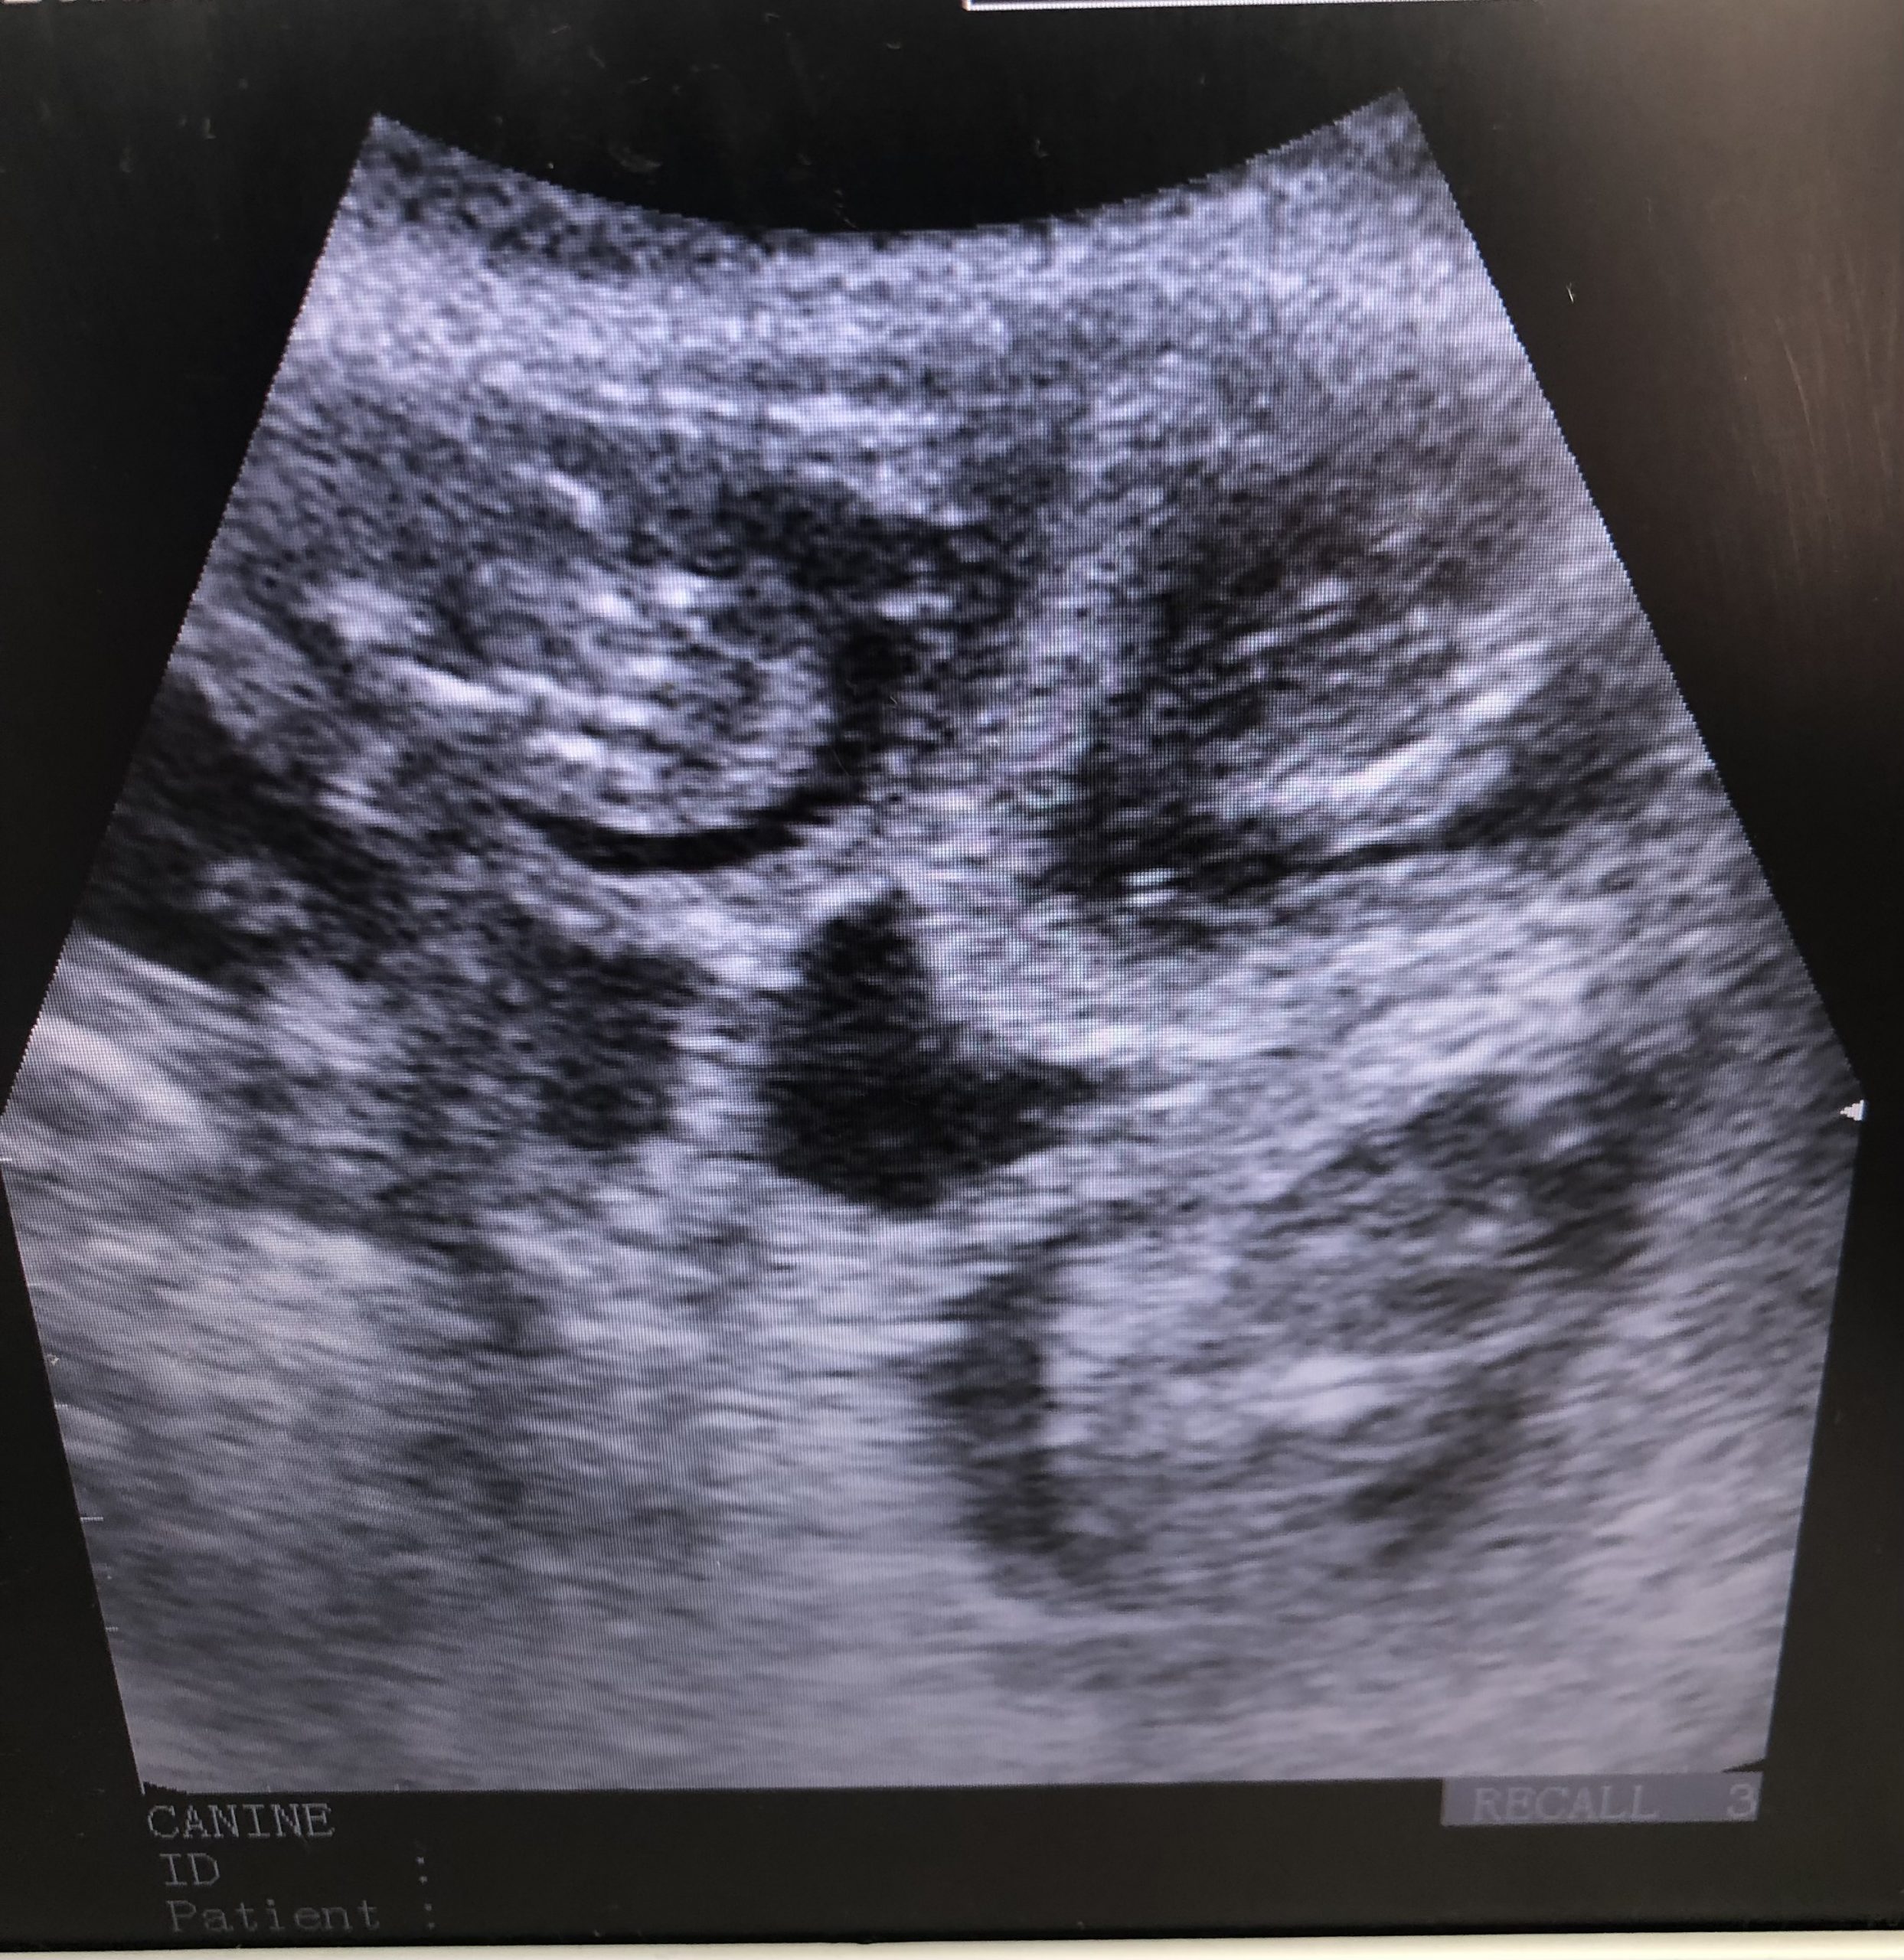

Nel, Dachshund Pregnancy Scan Conisbrough

Had the pleasure of meeting and scanning this girl. Pregnancy confirmed and we saw 6 gestational sacs. Excited to see these beauties born, sire is a very handsome black &